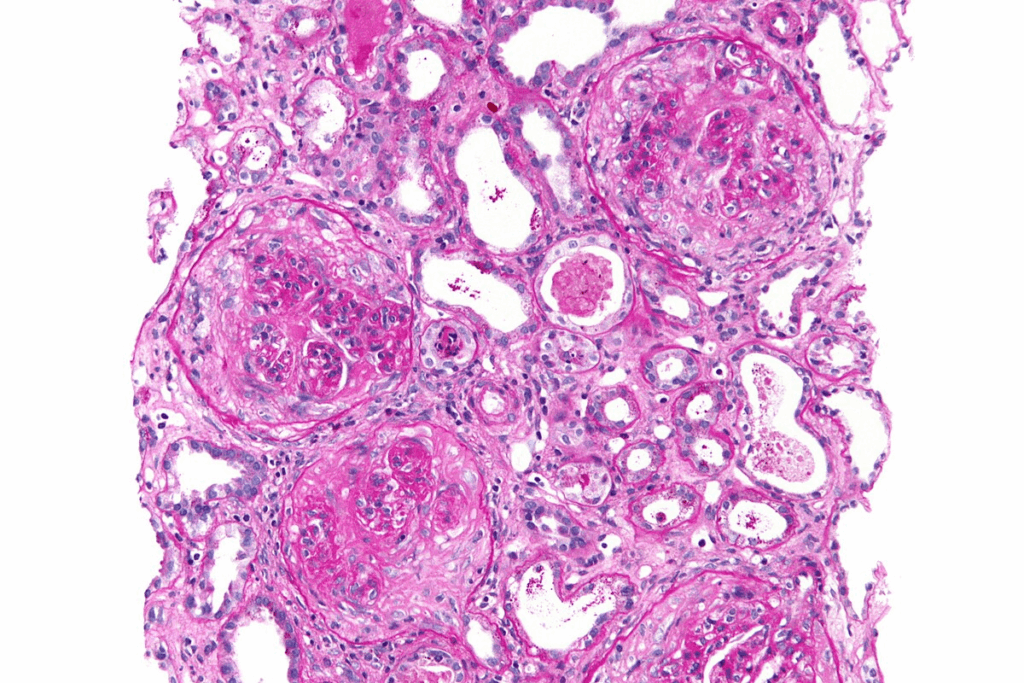

Understanding Glomerulonephritis and Its Impact on Kidney Function

Glomerulonephritis affects the tiny filters in our kidneys called glomeruli. These filters are key for keeping our fluids and waste balanced. They help remove waste and excess fluids from our blood, which is vital for our health.

What Are Glomeruli and How Do They Work?

The glomeruli are tiny filters in our kidneys. They let small molecules like water and glucose pass through. But they block bigger molecules like proteins and blood cells.

When the glomeruli work right, they filter waste and excess fluids well. But if they get damaged or inflamed, like in glomerulonephritis, they can’t filter properly. This can cause harmful substances to build up in our bodies, leading to symptoms and complications.